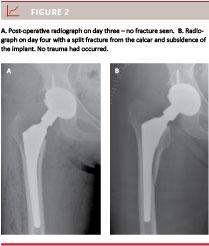

A total of 85 fractures were seen in the 3,295 patients (2.6%). A total of 2,408 of the patients had an uncemented femoral component with a fracture rate of 2.9% (69 patients). Forty-one of the 69 fractures in uncemented THAs were intraoperative cracks (Vancouver type A) which were usually treated with cerclage wires during the index operation (Figure 1). In 28 of the 2,408 uncemented cases (1.2%), a “new” type of fracture was seen. Immediate post-operative radiographs on the second or third day were normal, but seven (median) and 14 days (average) post-operatively, a sudden pain in the thigh without any trauma was experienced. Radiographs now showed a slightly displaced split fracture from the calcar region to the medial femoral shaft 8-10 cm below the lesser trochanter (Figure 2) with subsidence of the implant. Re-operation with exchange of the implant after internal fixation of the fracture with cables or a trochanteric grip was usually performed.